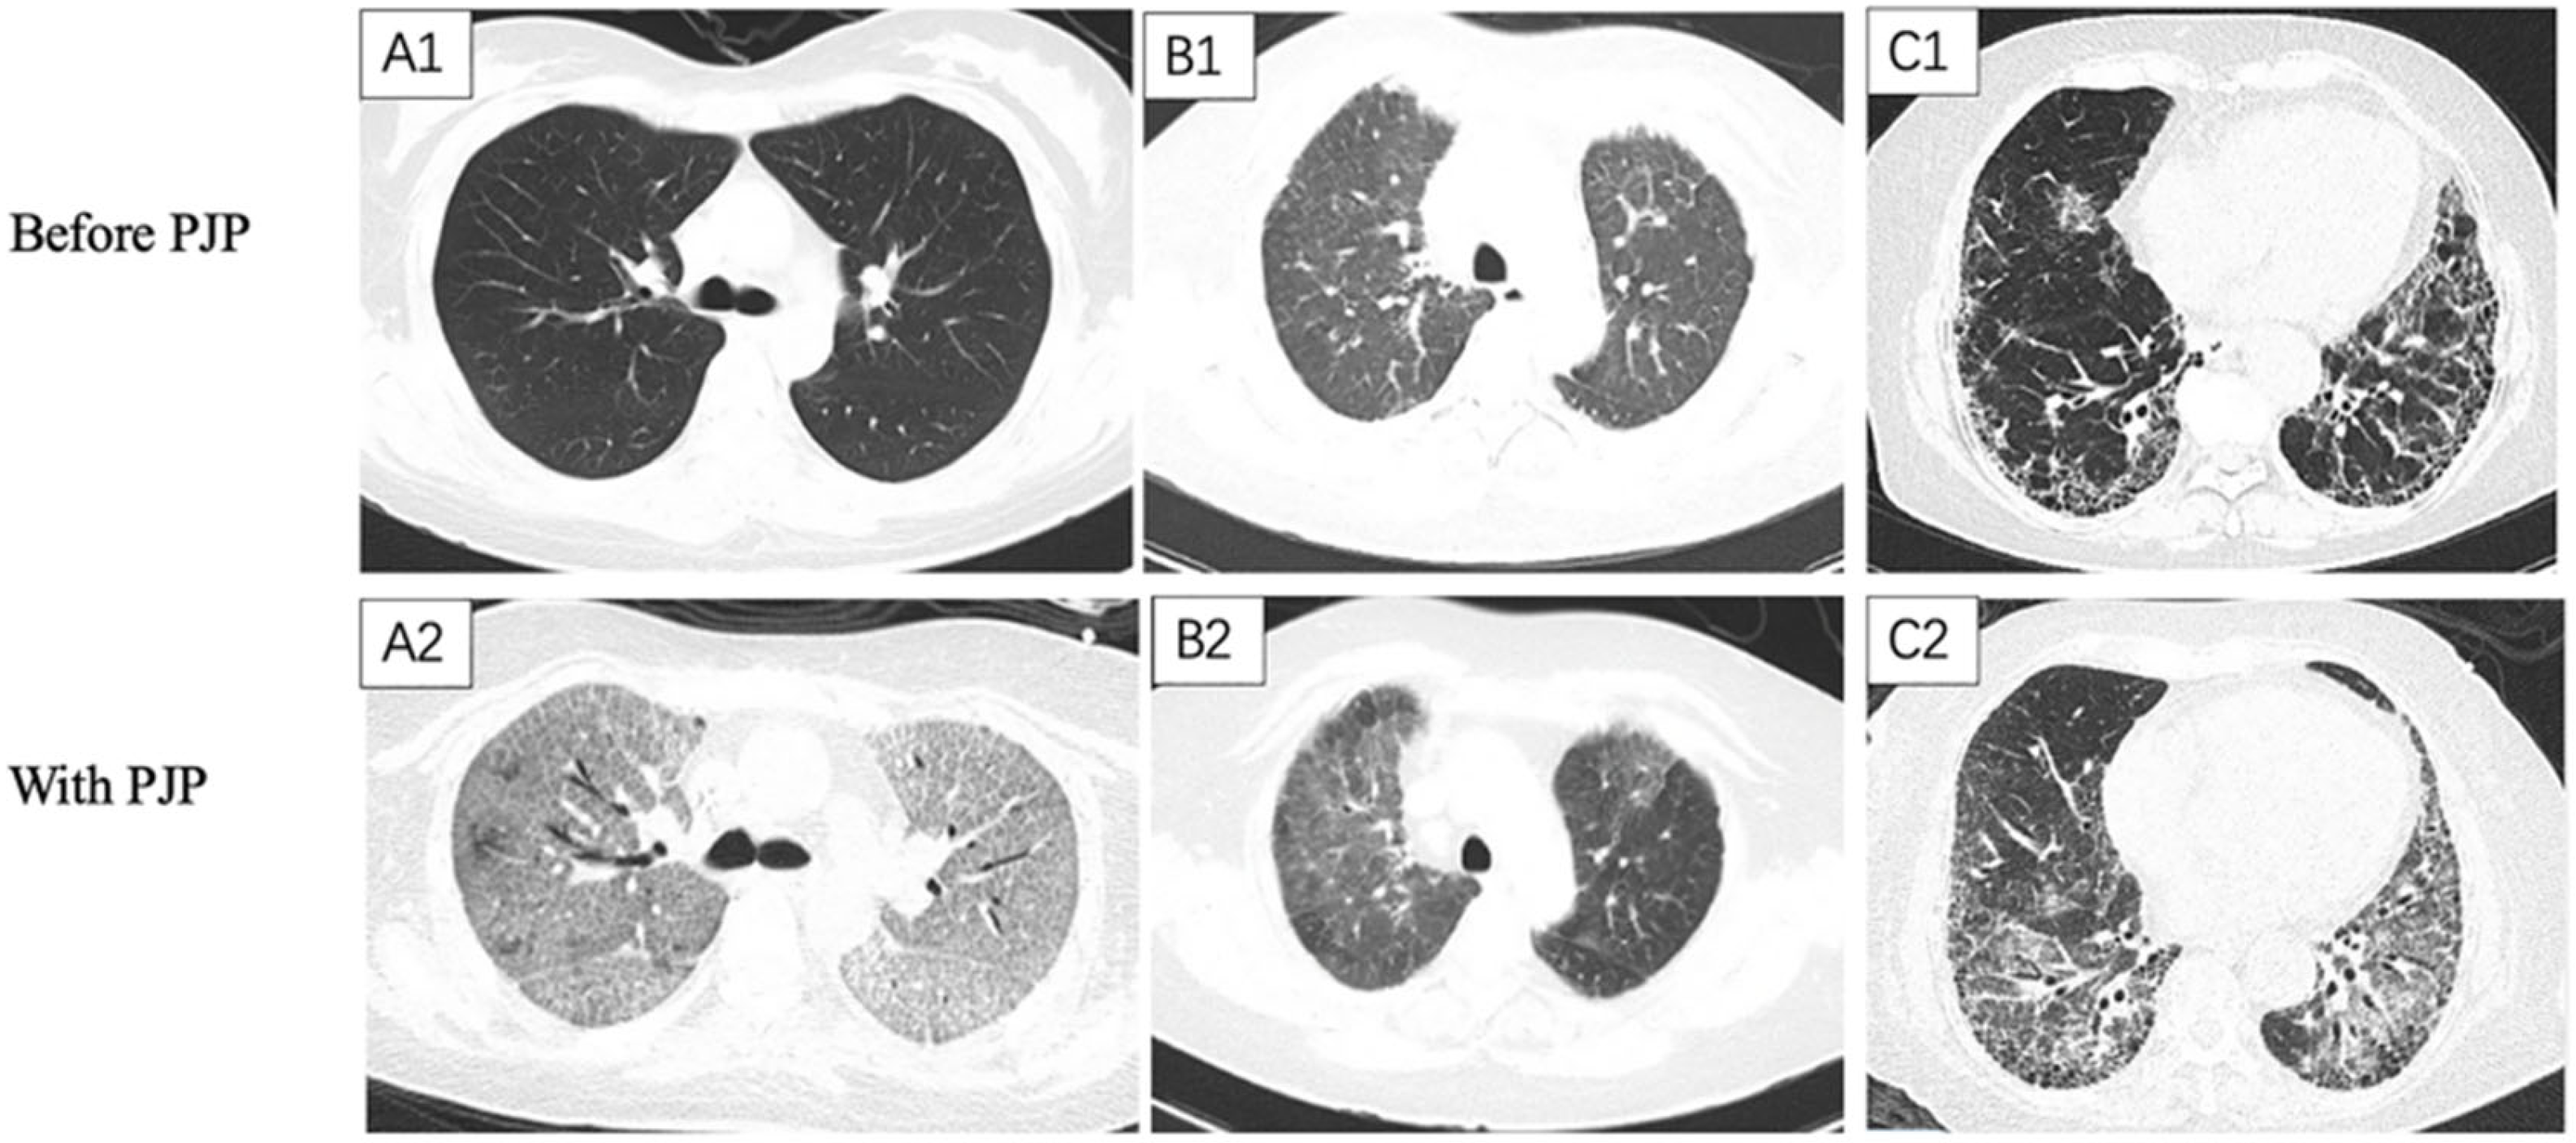

| Chest HRCT features | ||||

| Sub-pleural distribution (n/%) | 68/51.3% | 48/19.6% | 40.3 | <0.001 |

| Peri-bronchial distribution (n/%) | 13/9.8% | 22/9.0% | 0.06 | 0.8 |

| GGO (n/%) | 106/79.7% | 176/71.8% | 2.81 | 0.09 |

| Consolidation (n/%) | 36/27.1% | 106/43.3% | 9.64 | 0.002 |

| Reticular (n/%) | 50/37.6% | 17/6.9% | 55.5 | <0.001 |

| Honeycomb (n/%) | 19/14.3% | 1/0.4% | 33.1 | <0.001 |

| Nodular (n/%) | 46/34.6% | 112/45.7% | 4.39 | 0.036 |

| Septal thickening (n/%) | 39/29.3% | 16/6.5% | 36.0 | <0.001 |

| Pleural thickening (n/%) | 92/69.2% | 120/49.0% | 14.3 | <0.001 |

| Pleural effusion (n/%) | 43/32.3% | 101/41.2% | 2.89 | 0.09 |

| Lymphadenopathy (n/%) | 79/59.4% | 97/39.6% | 13.6 | <0.001 |